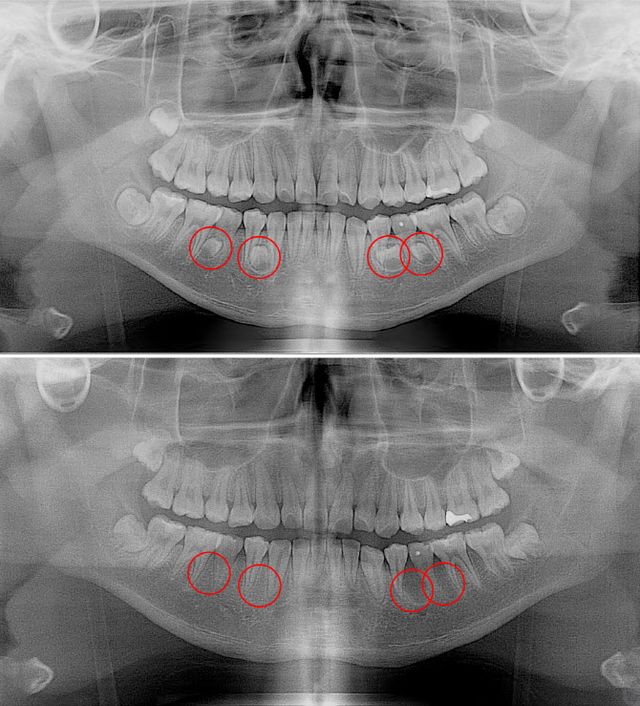

과잉치가 발생하는 정확한 원인은 밝혀지지 않았다. 다만 부모나 형제에게 과잉치가 있으면 발생 확률이 높아지는 것으로 보고 있다. 대부분이 턱뼈 내에 매복돼 있기 때문에 당사자 또는 보호자가 미리 알기는 매우 어렵다. 파노라마 방사선 촬영과 근단 방사선 사진 촬영, CT 촬영 등을 통해서만 발견할 수 있다.

과잉치는 발치가 가장 좋은 치료법이지만, 전문의가 구강 내 상황을 면밀히 살피고 결정해야 한다. 과잉치가 인접 영구치의 맹출에 영향을 크게 줄 것으로 예상되면 조기에 뽑아내지만, 이는 아무리 조심하더라도 주변 치아들에 영향을 줄 수 있기 때문에 일반적으로 인접 영구치의 치근이 어느 정도 성숙한 후에 발치를 결정하게 된다.